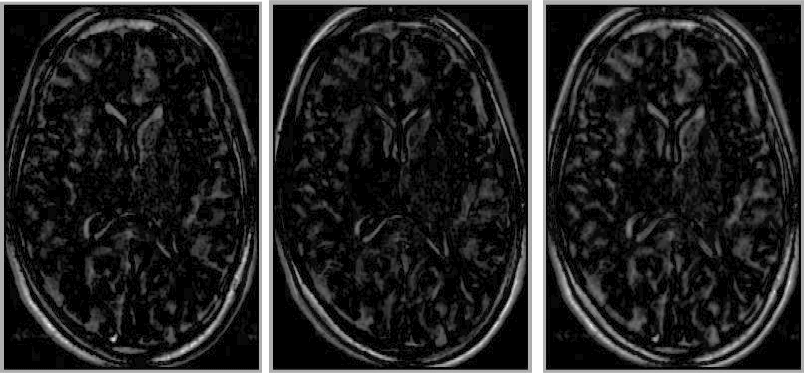

Figure: comparison between shuffle difference images evaluated using various size neighbourhoods (radius $r$). Left: original image, right: warped image, centre, from the left: shuffle difference images with $r=1$(Euclidean), $1.5,\,2.9$ and $3.7$ pixels.

Image shuffle_comparison-revised

It should be noted that the shuffle distance, as defined above, depends on the direction in which it is measured (see Figure [*]), hence is not a true distance. It is trivial to construct a symmetric shuffle distance, by averaging the distance calculated in both directions between a pair of images. I found empirically, however, that the improvement obtained in this way was not significant, and did not justify the increased computation time. In what follows, the asymmetric shuffle distance is used exclusively.

Figure: Examples of the shuffle difference image: from first to second (left), from second to first (centre), and the symmetrical shuffle difference image (right)

Image shuffle_images-revised